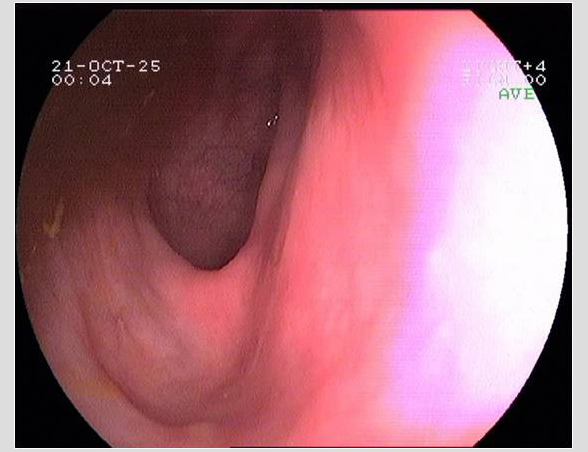

Imágenes tomadas durante la endoscopia digestiva alta y la colonoscopia. Se aprecia una mucosa de aspecto y vascularización normal, sin lesiones visibles. Se progresa con el colonoscopio hasta el íleon. Todo resulta macroscópicamente normal. Se toman biopsias de todos los segmentos explorados.

La endoscopia es el método de elección para el diagnóstico y seguimiento de la EII. Permite una visión macroscópica de la mucosa intestinal y la toma de múltiples biopsias para el estudio histológico.

Realizamos una endoscopia digestiva alta y una colonoscopia a la paciente con toma de biopsias, obteniendo el informe de Anatomía patológica.